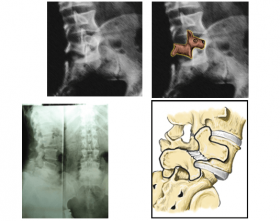

Nhận biết trượt đốt sống và cách chữa trượt đốt sống